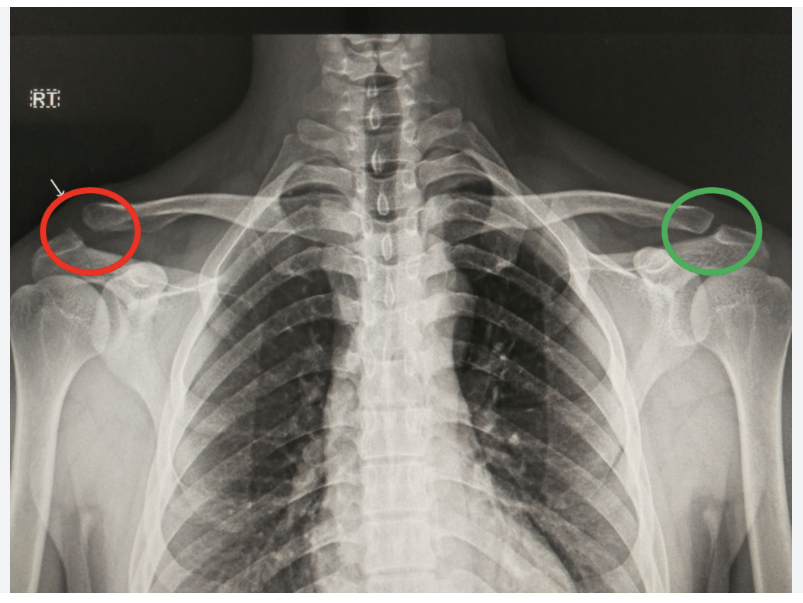

AC joint seperation

Trauma in upper shoulder resulting in a partial or complete tear of the AC.

Dislocation

when bones at a joint separate from their normal positions, often caused by trauma, leading to intense pain, swelling, deformity, and inability to move the joint